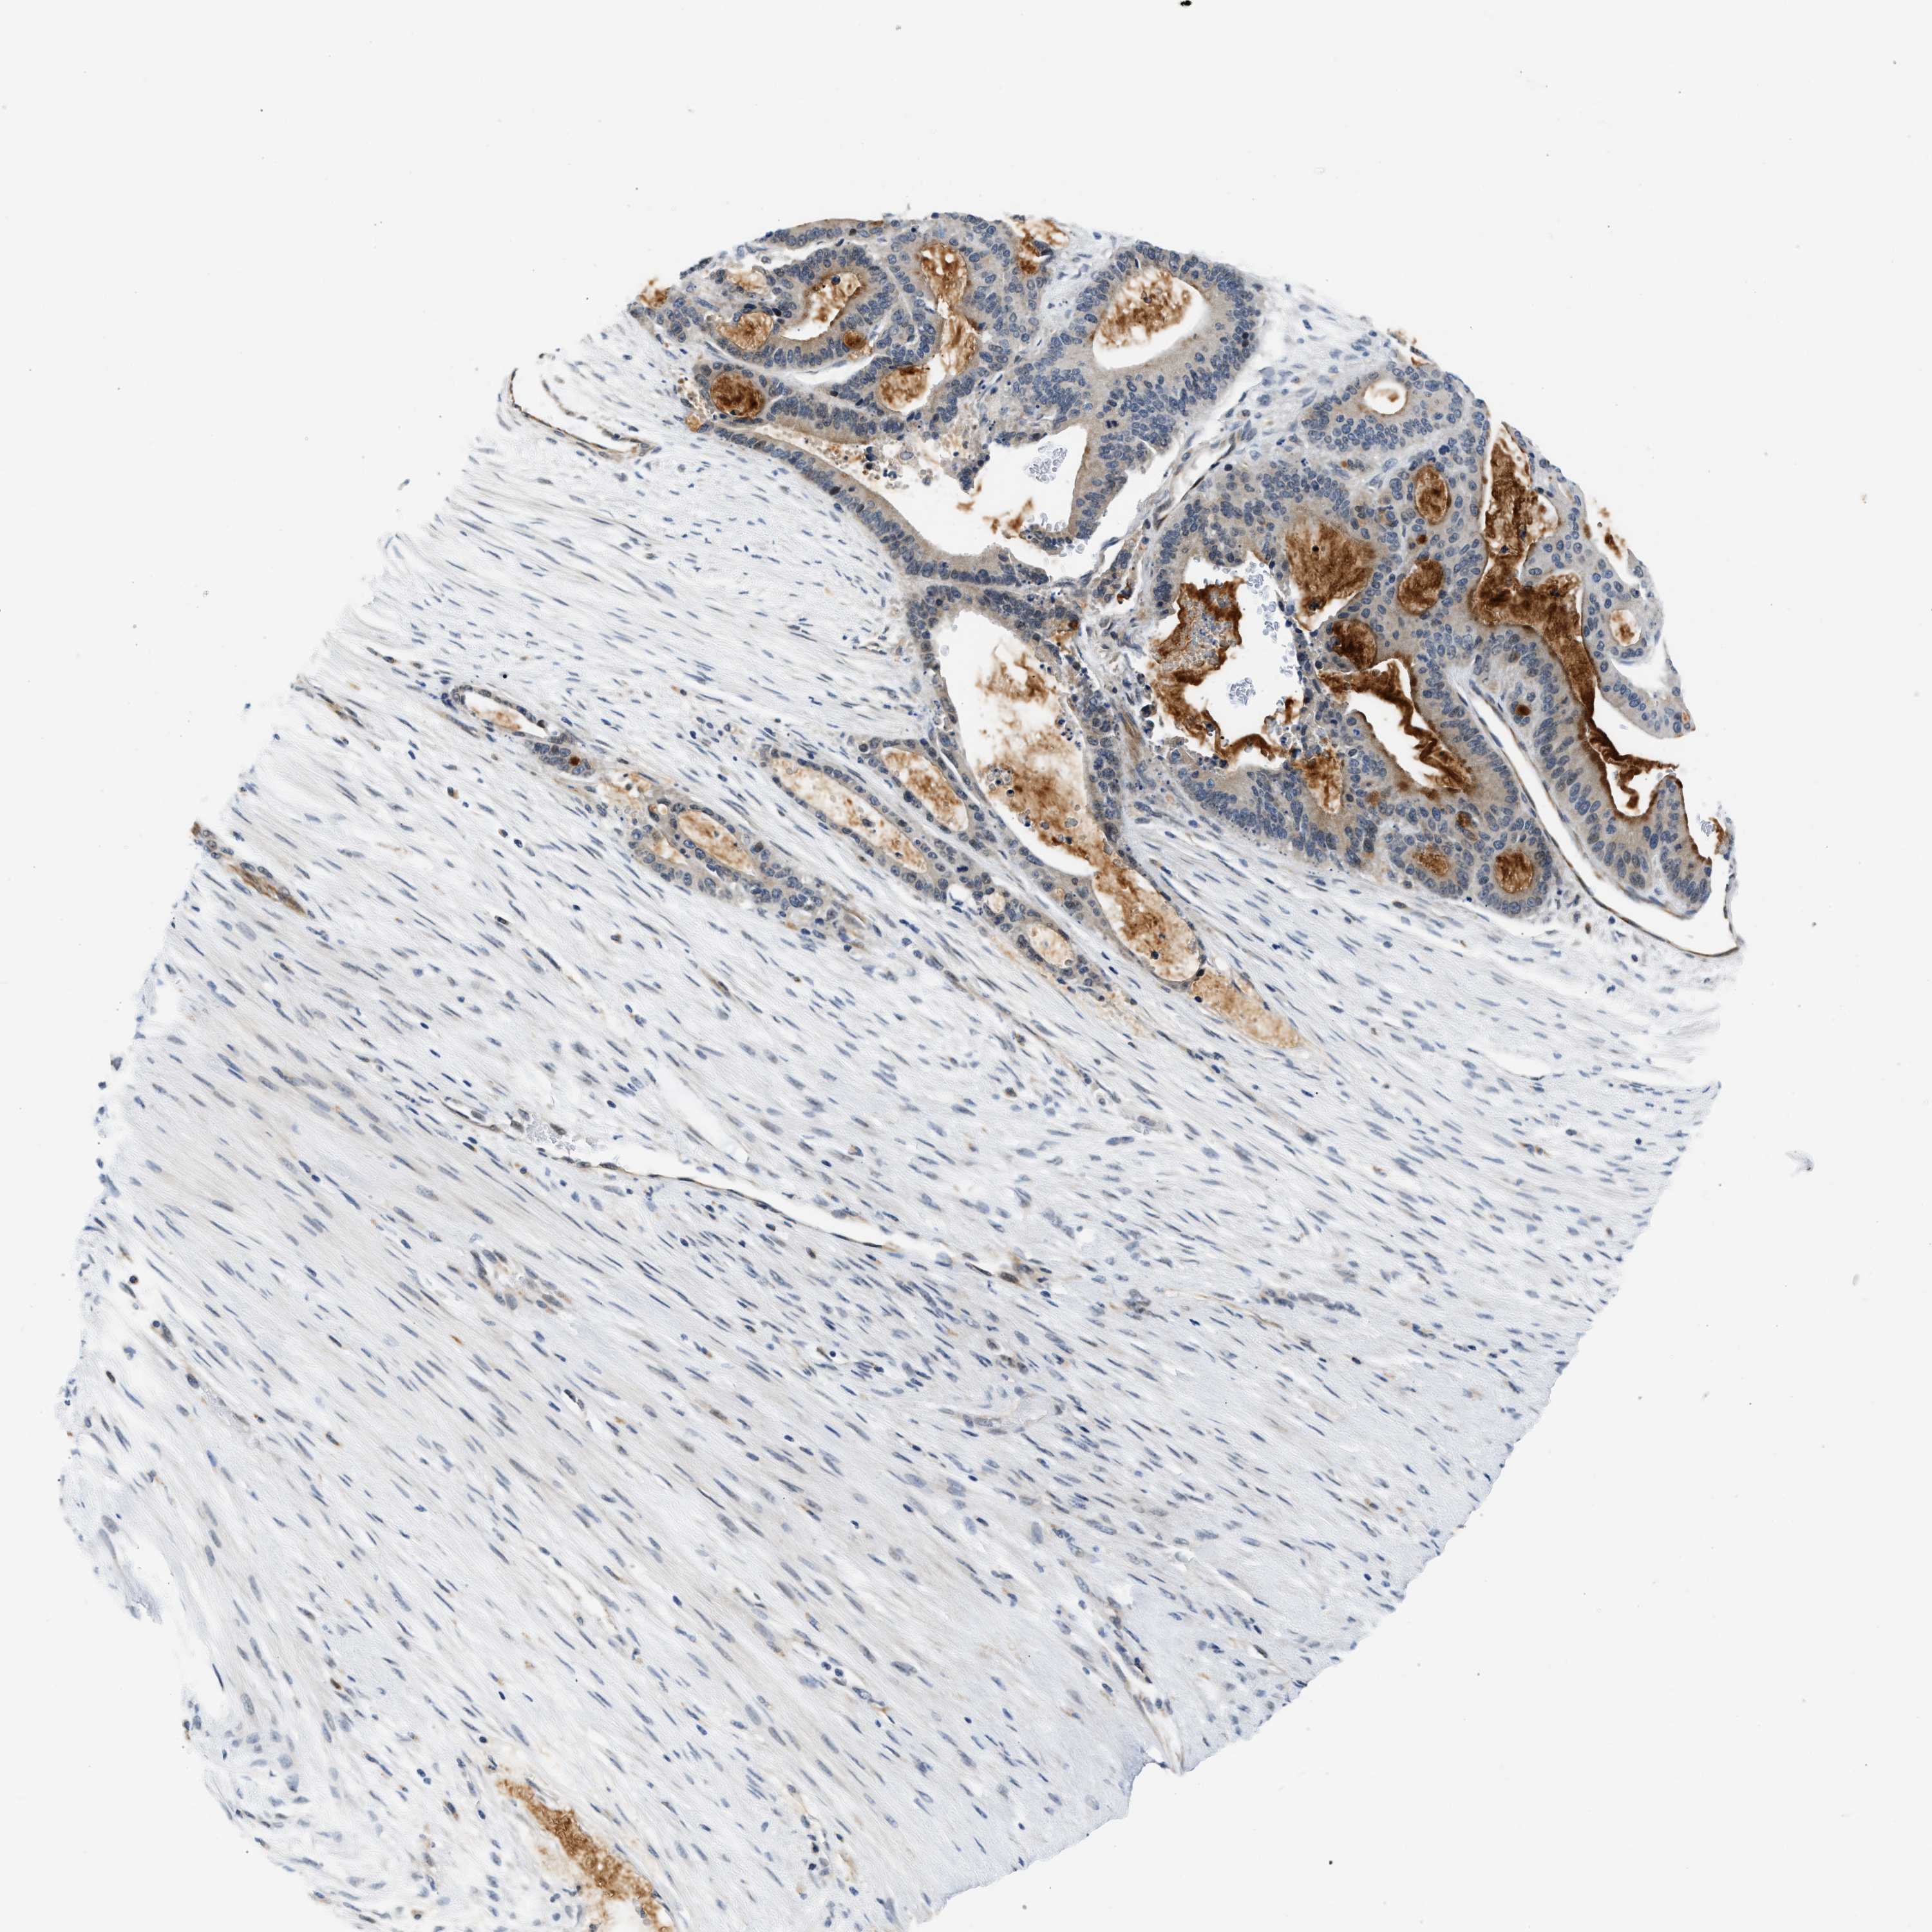

LIVER CANCER - Protein expressioni

A mouse-over function shows sample information and annotation data. Click on an image to view it in a full screen mode. Samples can be filtered based on level of antibody staining by selecting one or several of the following categories: high, medium, low and not detected. The assay and annotation is described here.

Antibody stainingi

Antibody staining in the annotated cell types in the current human tissue is reported as not detected, low, medium, or high, based on conventional immunohistochemistry profiling in selected tissues. This score is based on the combination of the staining intensity and fraction of stained cells.

Each image is clickable and will lead to virtual microscopy that enables deeper exploration of all samples and also displays staining intensity scores, fraction scores and subcellular localization as well as patient and tissue information for each sample.

Antibody HPA044244

Antibody HPA058777

Antibody CAB020694

Staining

High

Medium

Low

Not detected

Intensity

Strong

Moderate

Weak

Negative

Quantity

>75%

75%-25%

<25%

None

Location

Nuclear

Cytoplasmic/membranous

Cytoplasmic/membranous,nuclear

Cholangiocarcinoma

Carcinoma, Hepatocellular, NOS